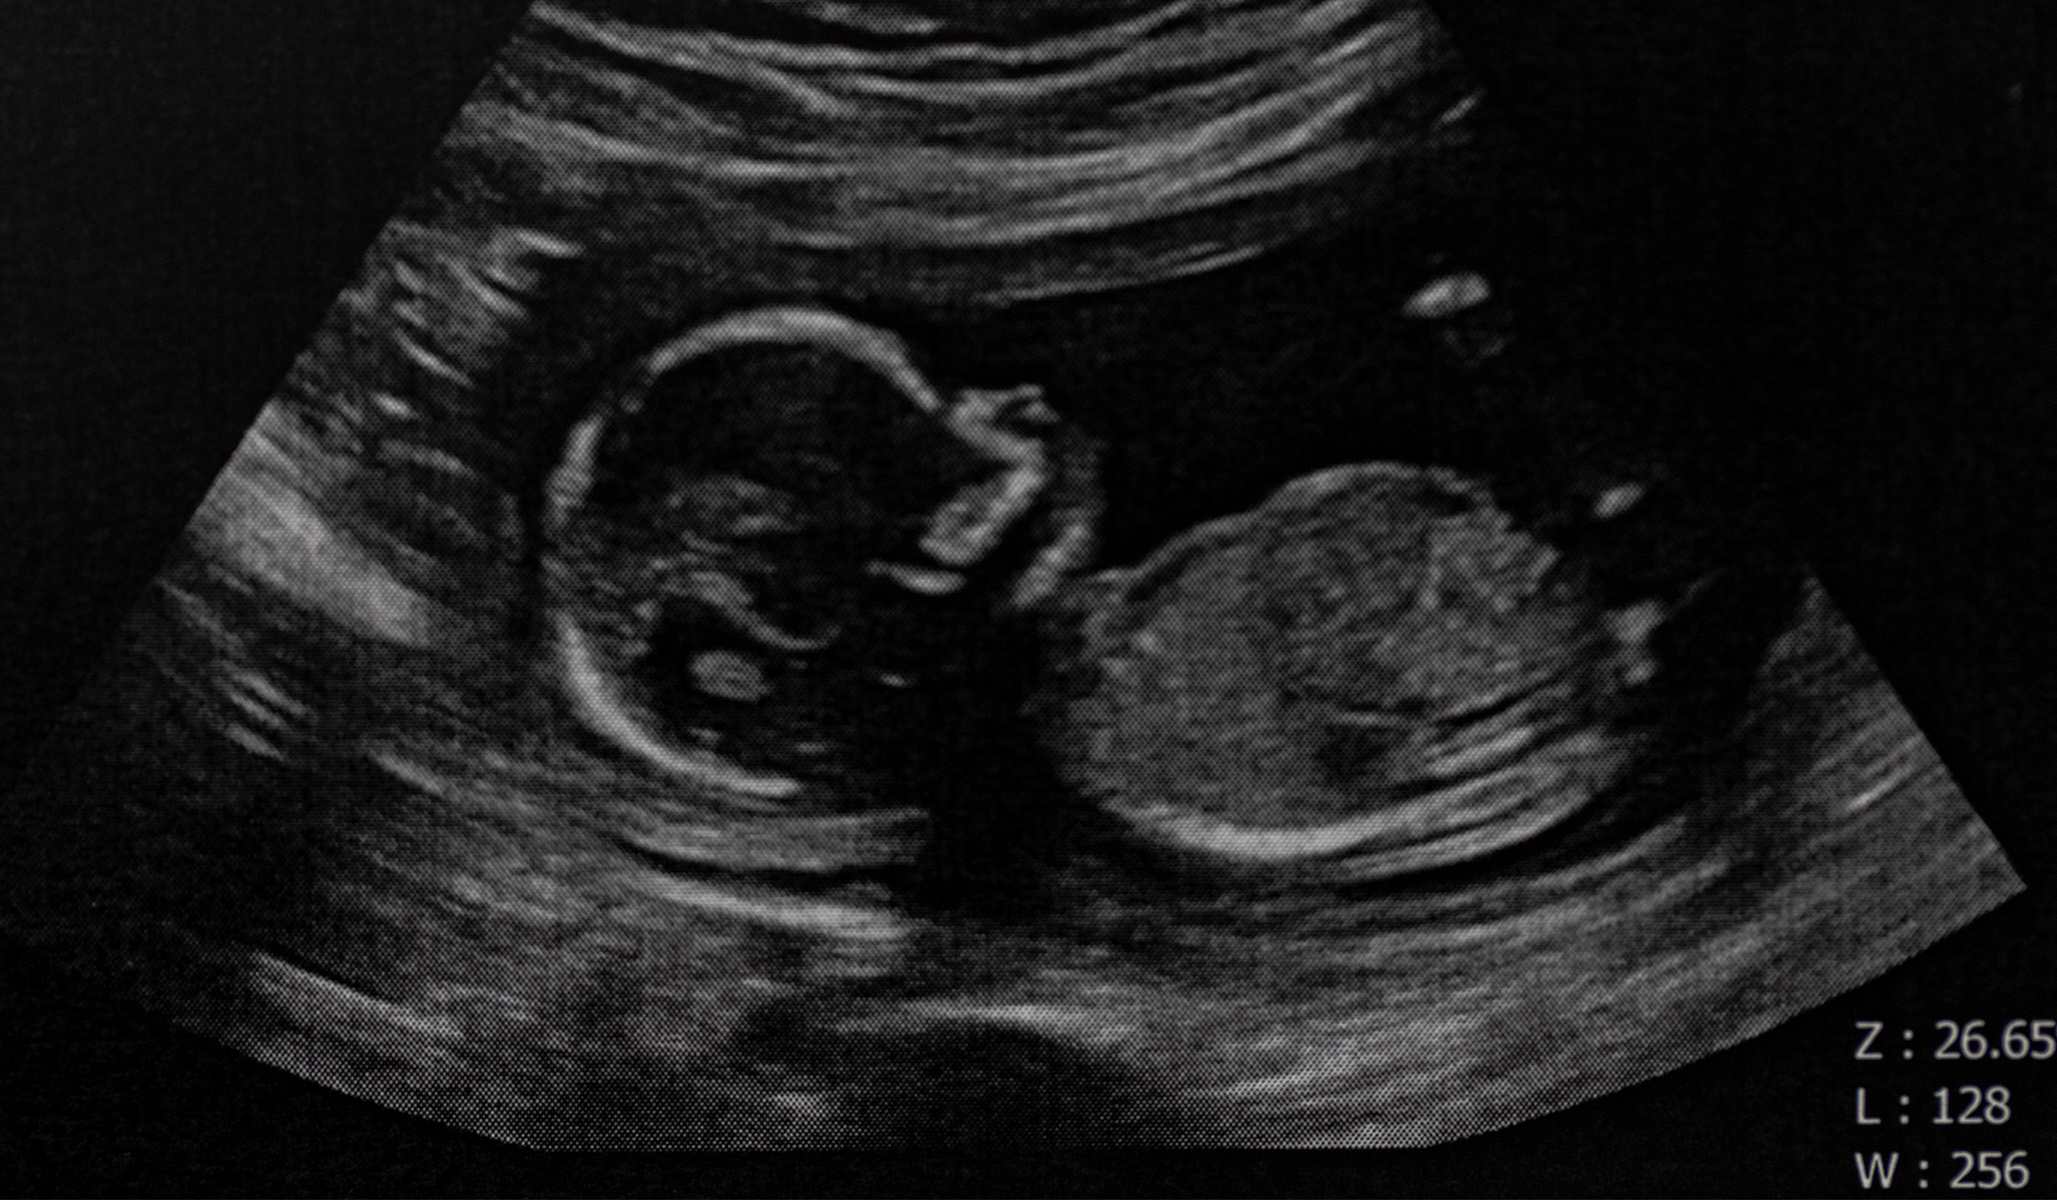

Hence then, the article about abortion and the eyeball test was published today ( ) and is available on National Review ( Middle East ) The editorial team at PressBee has edited and verified it, and it may have been modified, fully republished, or quoted. You can read and follow the updates of this news or article from its original source.